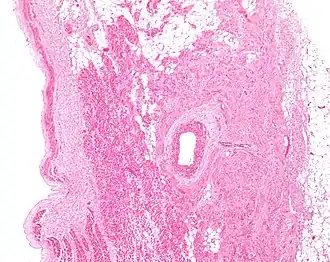

Figure 2: Low magnification stained image of the SA node (center-right on image) and its surrounding tissue. The SA node surrounds the sinoatrial nodal artery, seen as the open lumen. Cardiac muscle cells of the right atrium can be seen to the left of the node, and fat tissue to the right.

The cells of the SA node are spread out within a mesh of connective tissue, containing nerves, blood vessels, collagen and fat. Immediately surrounding the SA node cells are paranodal cells.[2] These cells have structures intermediate between that of the SA node cells and the rest of the atrium.[6] The connective tissue, along with the paranodal cells, insulate the SA node from the rest of the atrium, preventing the electrical activity of the atrial cells from affecting the SA node cells.[2] The SA node cells are smaller and paler than the surrounding atrial cells, with the average cell being around 8 micrometers in diameter and 20-30 micrometers in length (1 micrometer= 0.000001 meter).[7] Unlike the atrial cells, SA node cells contain fewer mitochondria and myofibers, as well as a smaller sarcoplasmic reticulum. This means that the SA node cells are less equipped to contract compared to the atrial and ventricular cells.[8]